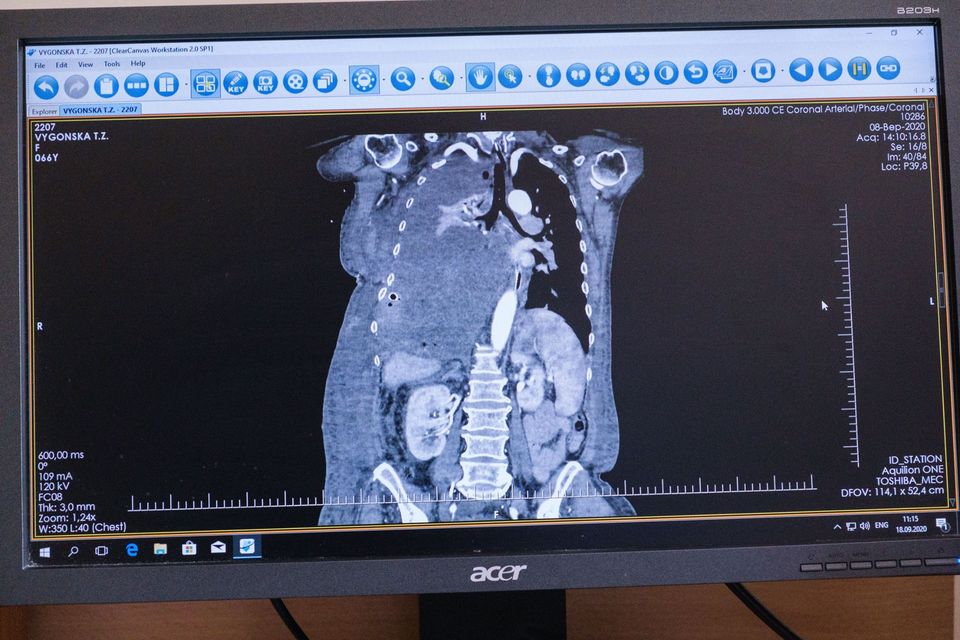

В субботу, 19 сентября, стало известно о том, что медики в больнице "Феофания" провели уникальную операцию, во время которой удалили из грудной клетки 66-летней Татьяны Выгонской опухоль весом 4,5 кг.

"В мае Татьяна Выгонская почувствовала сильную одышку и слабость, поэтому была вынуждена обратиться за медицинской помощью по месту жительства, а оттуда ее отправили в Хмельницкую областную клиническую больницу, где провели обследование и взяли ряд анализов. Диагноз - солитарная фиброзная опухоль правого гемиторакса. Новообразование было таким большим, что срослось, зажало правое легкое и давило на левое легкое и сердце. Из-за размера опухоли женщину отказались оперировать, а местный онколог посоветовал проконсультироваться у хирурга Виталия Соколова в Киеве", - говорится в тексте сообщения.

В "Феофании" медики провели операцию по удалению 4,5-килограмовой опухоли. Фото: facebook.com/president.gov.ua